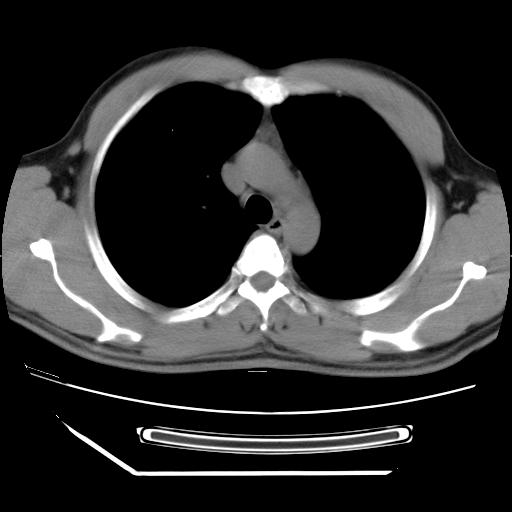

男,38岁,于2009年8月9日晚突发左侧胸痛,今x线提示左下肺阴影,为了明显确诊断,行ct检查,

血常规:嗜酸性细胞增高,单核细胞增高。

病灶发生在下叶,密度均匀,边缘模糊、毛糙,周围血管纹理增强扭曲改变,靠近胸膜处病灶胸膜反应明显。

支持考虑---球形肺炎。

左肺舌叶病变。主体病灶呈类圆形中心密度低,成液化趋势周边班片影分布

考虑肺脓肿

虽然实验室检查支持炎性病变,且病变内有坏死改变(中央呈大片状低密度影),但仍不能掉以轻心,鳞癌也可以有这种影像改变。